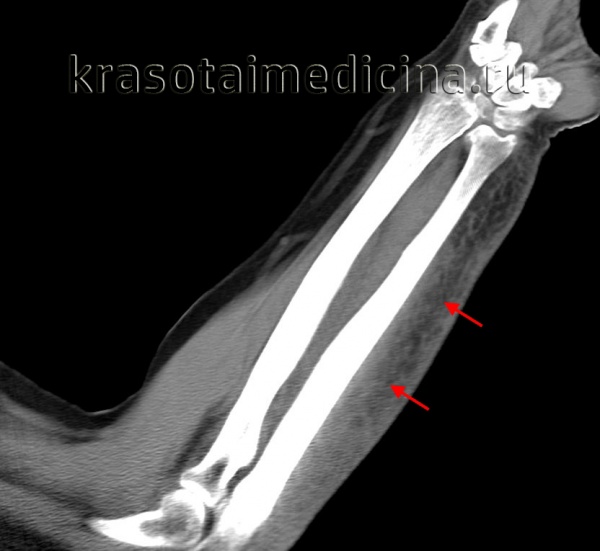

image

КТ предплечья. Геморрагическое пропитывание и отек мягких тканей предплечья со стороны лучевой кости (ушиб, подкожная гематома).